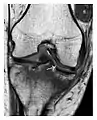

- a

- b

- c

Figure 1: A 56-year-old woman presenting with left knee pain after a fall. (a) Initial anteroposterior radiograph was considered normal, however, subtle cortical disruption of the anterior rim of the medial tibial plateau, medial to the tibial spine, is noted (arrow). (b) Coronal T1-weighted MRI confirms the cortical disruption (arrow) and shows extensive fracture through the proximal tibia. (c) Coronal proton density-weighted image with fat saturation shows extensive edema in the subchondral bone. Note also hypersignal adjacent to the medial collateral ligament corresponding to a grade I sprain (arrowheads).[1]